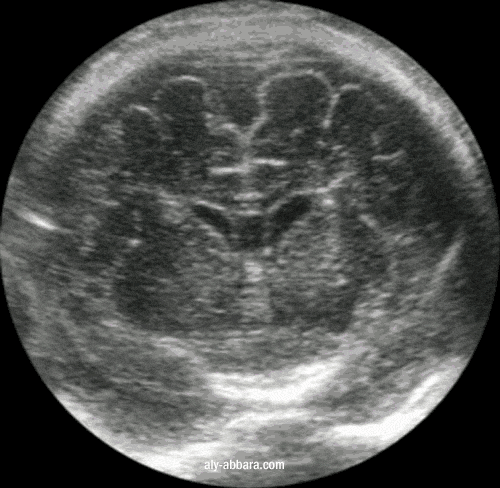

Coupe frontale du cerveau fœtal à 39 SA

passant par le corps calleux au niveau

du cavum septum pellucidum

On met en évidence le corps calleux, les cornes frontales des ventricules latéraux, le cavum du septum pellucidum,

la tête des noyaux caudés, la capsule interne, les putamens, le gyrus subcalleux et les circonvolutions péri-calleux

A comparer la même coupe réalisée par IRM (Imagerie par Résonance Magnétique) fœtale à 32 SA